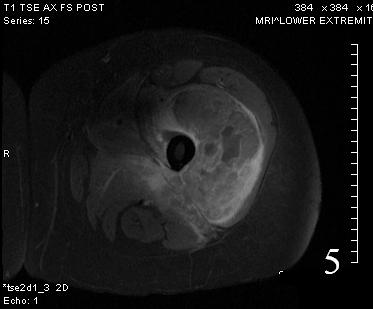

GENERAL INFORMATION Tumoral calcinosis is a very rare entity, characterized by large tumorlike calcium deposits and painless mass, arising near to the articular soft tissue areas. Common areas affected are elbows, hips, knees rarely involve hands and feet. No obvious...